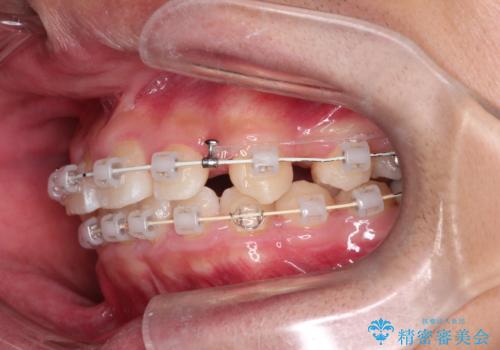

八重歯・歯並びのデコボコとディープバイトを改善した抜歯ワイヤー矯正症例

- 八重歯と咬み合わせを治したいを主訴にご来院された患者様です。

矯正の精密検査の結果上顎左右4番の計2本を抜歯し、審美性に配慮したワイヤー矯正装置(審美装置)を用いて治療を行いました。

八重歯などの歯列のデコボコが綺麗に改善され、患者様にも大変喜んでいただけました。また、咬み合わせが深い「ディープバイト」も併せて改善し、見た目だけでなく機能面でもバランスの取れた咬合を獲得しています。